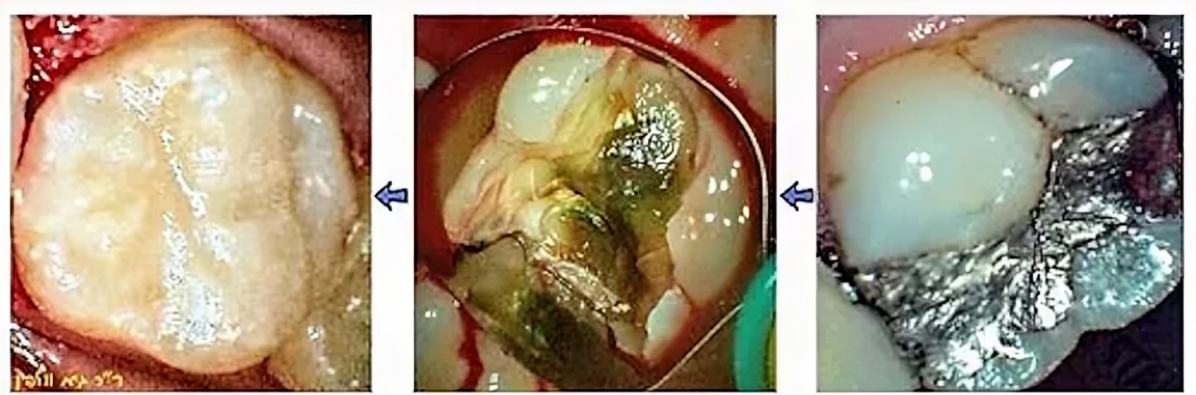

פעמים רבות בגלל הזנחה או חוסר מודעות מתפתח חור עמוק מאוד בשן, לעיתים אף ללא הרגשת כאב, במיוחד אם החור מתפתח מתחת לסתימה ישנה. בצילום הרנטגן ובבדיקה הקלינית הרופא מגיע למצב של דילמה – החור מאוד עמוק, אך עדיין אין דלקת בעצב שמחייבת טיפול שורש. האם הרופא יבחר בטיפול שורש + מבנה + כתר (שהוא גם הפיתרון היקר יותר), או בפתרון שמרני יותר (שהינו זול בהרבה), והוא לבצע טיפול מיוחד שנקרא "כיפוי מוך" ולאחריו סתימה נרחבת מקומפוזיט תוך כדי שיחזור האנטומיה המקורית של השן לפני שנפגעה מהחיידקים ומהריקבון. תמיד כדאי לשאול את הרופא אם עוד ניתן לבצע כיפוי מוך, או שכבר מאוחר מדי. מעבר לעניין הבריאותי (כיפוי מוך ושיחזור שן מותיר את השן חיה, עם תחושה), עלות הטיפול זולה בהרבה מאשר טיפול שורש + מבנה + כתר.

בתהליך כיפוי (=כיסוי) המוך, במידה והרופא איבחן שיש חור מאוד עמוק אך ככל הנראה עוד אין דלקת בעצב, רופא מנוסה ושמרני ינסה להציל את השן ולא מיידית להחליט על טיפול שורש או רק לעשות "סתימה": הרופא מורח באיזור העמוק ביותר חומרים מיוחדים שתפקידם לחסל חיידקים ולחזק את האיזור, ולבודד את איזור העצב שנחשף מחשיפה לאוויר ולחיידקים, למשל Theracal שמעודד בניית השן מחדש באיזור הפנימי ע"י שיחרור  calcium silicate וחומרים אנטיבקטריאליים אחרים. כמו כן נמרחים גם חומרים אחרים לחיטוי/ניקוי/הפחתת הרגישות שאופיינית לחורים עמוקים מאוד.

רק לאחר ביצוע כיפוי המוך ימשיך הרופא ויבצע את שיחזור השן והאנטומיה המקורית. כיפוי המוך הנ"ל משפר את הסיכוי של הצלחת הסתימה, לעומת סתימה "רגילה" עמוקה וללא כיפוי מוך. כמובן כל זאת בתנאי שעדיין לא מתפתח דלקת בעצב, נמק או זיהום.